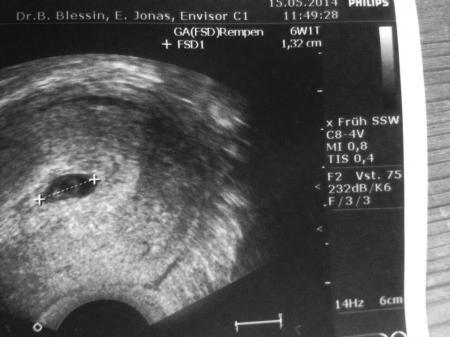

Bei mir war bei 6+0 alles da inklusive Herzschlag und so sah es aus

Bild zu